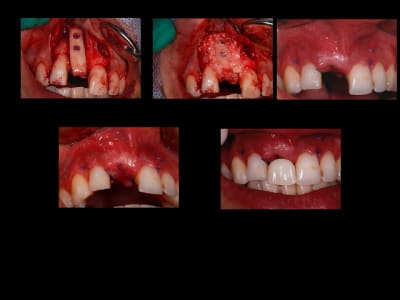

encore un ptit cas...sympa si on veut...car là j'ai besoin de l'expérience de ceux qui font çà souvent...

patient 17 ans...bientôt 18...

trauma dans l'enfance sur 11 et 21

pour la 21, çà va...mais la 11 est à bout de souffle...avec l'apex qui traverse la gencive vestibulaire...

veut un implant...forcément...mais là, faut une greffe...plutôt importante...

Planche1 nb4u3t - Eugenol

Planche2 awlu7r - Eugenol